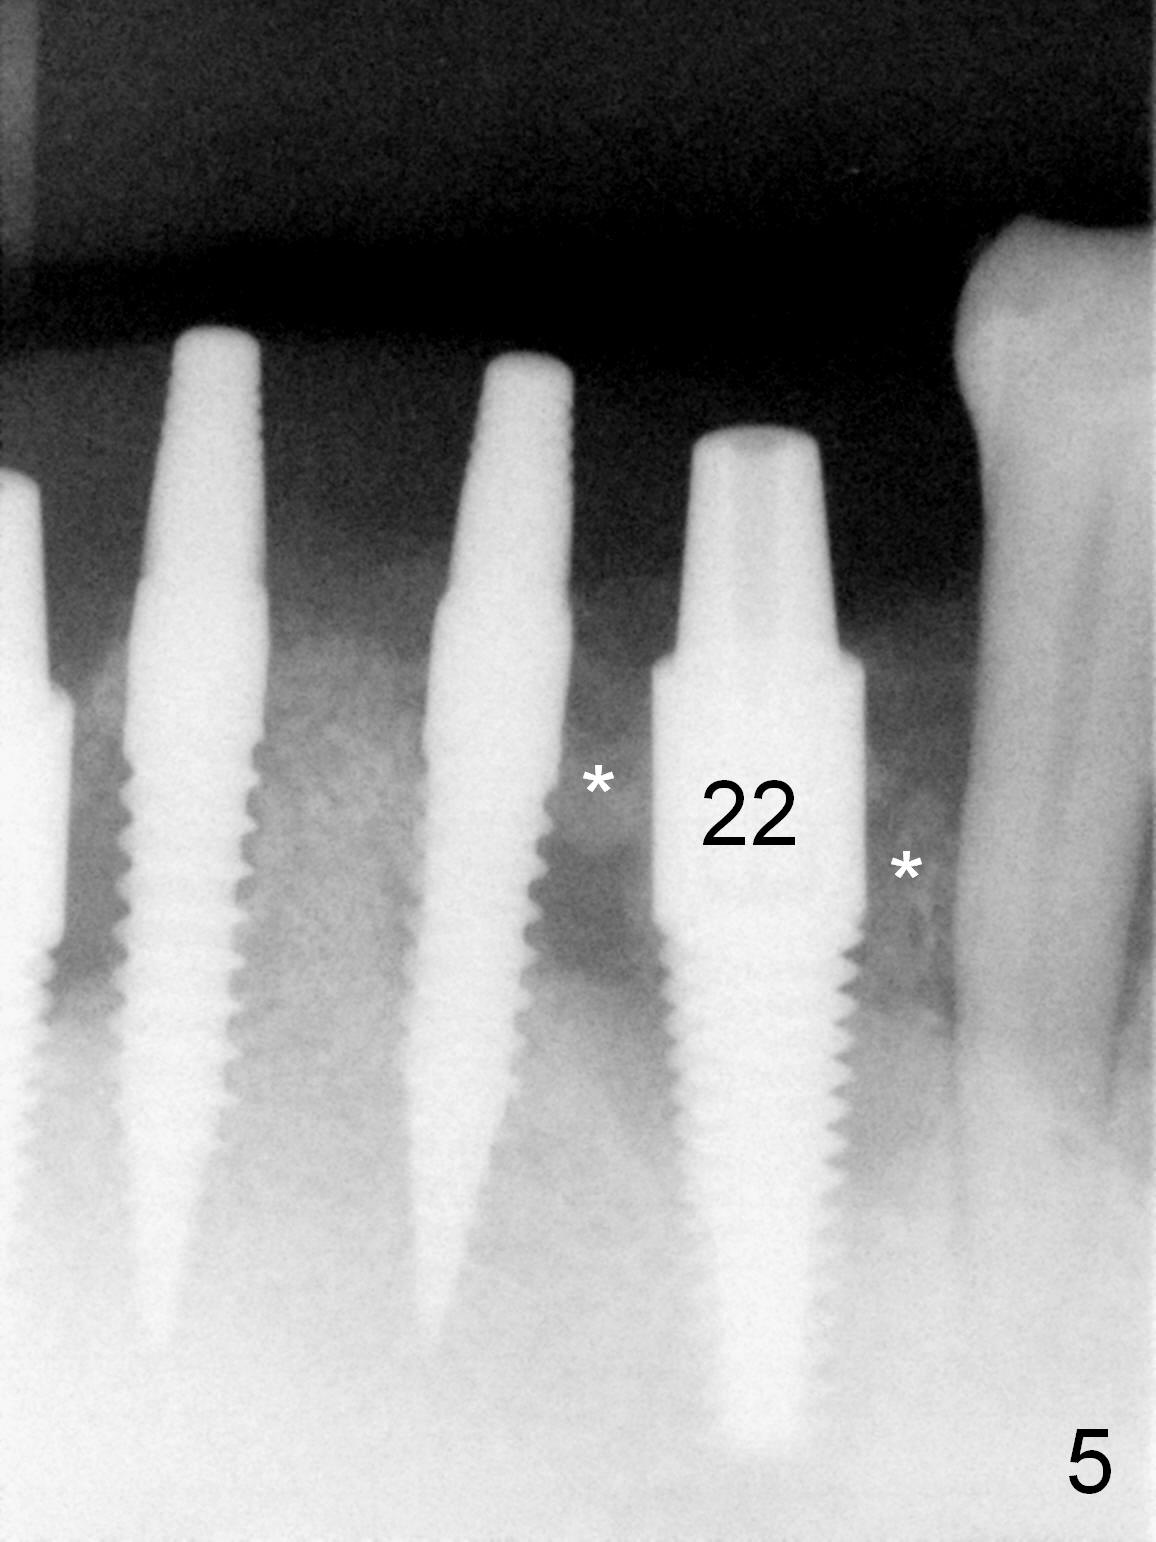

As expected, the bone density in the mandibular anterior region is found to be high during initial osteotomy (Fig.1-3). Five implants are placed at the sites between #22 and 28 (Fig.4,5): 3x14(2) mm 1-piece (bone-level) implants in the incisor region; 4.5x17 mm 2-piece (tissue-level) ones in the canine/premolar area. All of the implants are placed as lingual as possible. Bone graft is placed (*). Red dashed line: the superior border of the Inferior Alveolar Canal. Immediate splinted provisional bridge is fabricated. One week postop, periodontal dressing remains attached to the provisional and the gingiva.